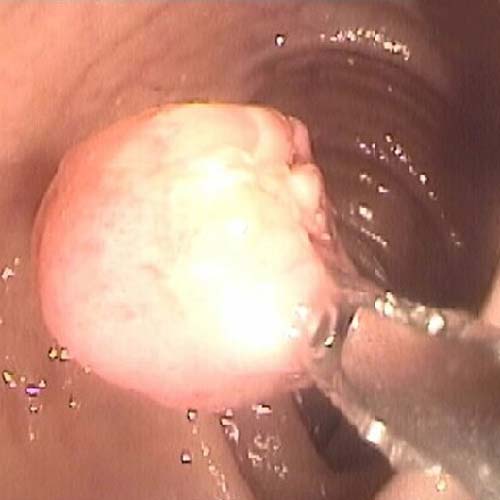

Procedimiento ambulatorio para detectar hemorragias digestivas, extirpación de pólipos, enfermedad de la vía biliar, extracción de cálculos, patología de colon o intestino delgado.

Procedimientos para visualizar el colon, tanto lumen como la mucosa, para tomar biopias o efectuar extirpación de pólipo, dilataciones, detención de un sangramiento y otras.